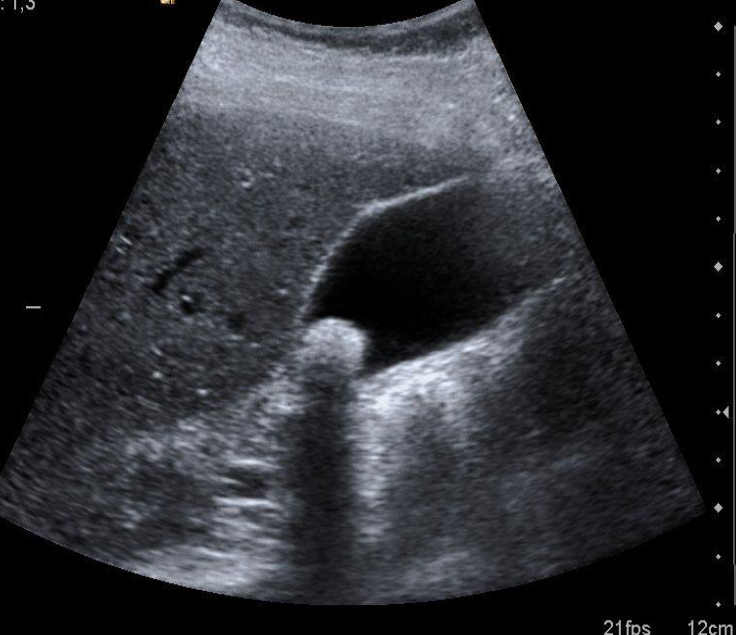

Diagnosis of Cholelithiasis

Hyperechoic shadow from stone - wall is normal